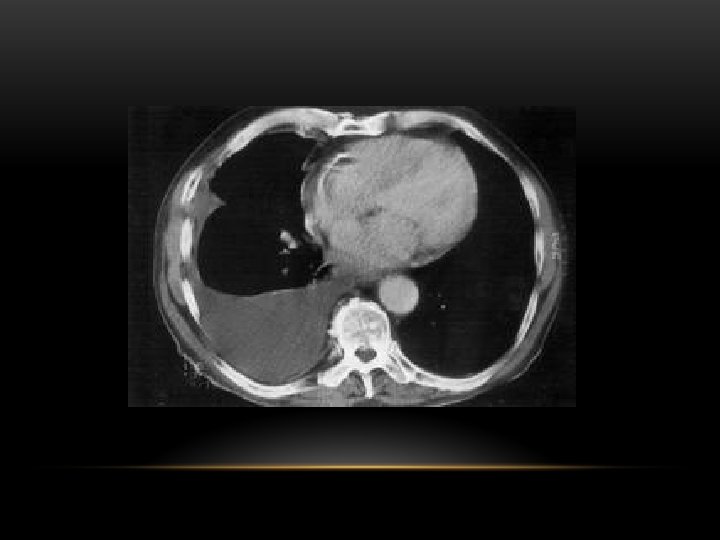

Pleural Effusion Fluid accumulates in the pleural space. Irrespective of the nature of fluid, radiologically they will look similar. Radiological criteria are: Density In dependent portion (Costophrenic angle in PA view). Blunting of costophrenic angle Lack of identifiable diaphragm (silhouette sign principle).

Causes of pleural effusion: -Infection -Subphrenic abscess. -Malignant neoplasm -Cardiac failure -Pulmonary infarction -Collagen vascular disease -Nephrotic syndrom Modalities for pl. effusion diagnosis: -Plain chest x ray. -Ultrasound -Computed tomography

CT scan of left empyema with pleural enhancement

loculated pleural effusion